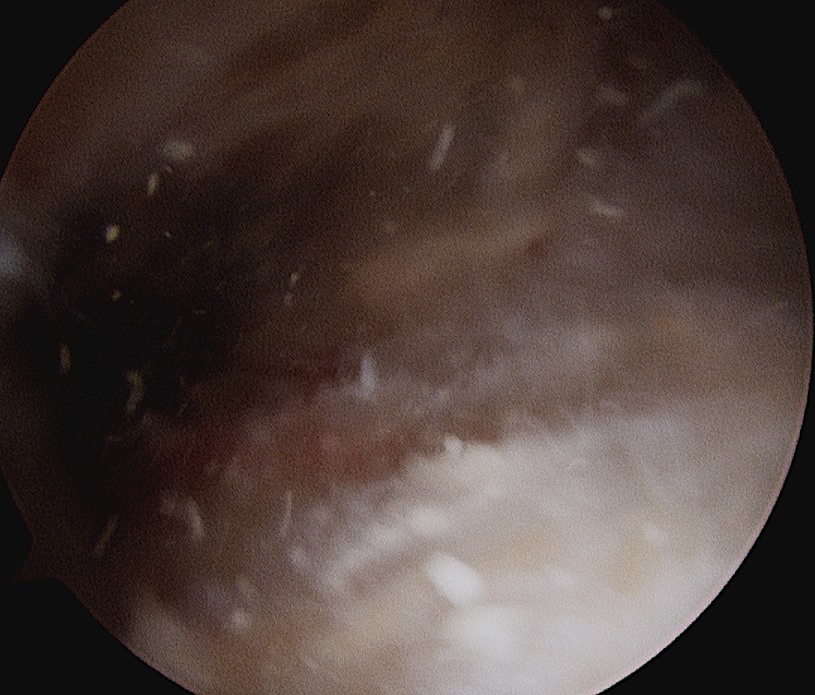

Arthroscopic Technique

Technique

Locate calcium lump

- remove bursa with shaver

- deposit may be obvious

- however may have to use needle: get cloud of calcium when find deposit

- longitudinally split tendon and currette calcium

- repair rotator cuff

Calcium NoduleCalcium Needle

Location of calcium deposit under vision and with needle

Calcium IncisionCalcium in TendonCalcific Tendonitis Arthroscopy 4

Longitudinal incision of rotator cuff / debridement of calcium / rotator cuff repair